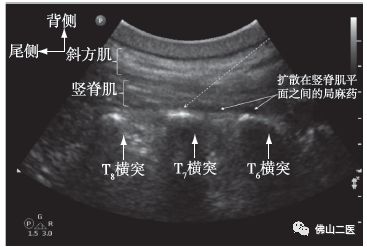

竖脊肌平面(ESP)阻滞是一项新颖的技术,最显著的优点就是操作简单并且安全,操作时横突及肌肉间隙图像容易识别。与硬膜外镇痛相比,它不会带来气胸、硬膜外血肿、脊髓损伤等风险,对凝血功能要求较小,对循环和呼吸功能影响也较少;与镇痛药物相比,它无呼吸抑制,不会引起恶心呕吐、成瘾、耐药等不良反应。

“由于竖脊肌覆盖整个背部,因此ESP阻滞可以使局麻药物在头尾方向广泛扩散并覆盖多个皮节感觉区域。另一方面,由于ESP的阻滞位置靠近横突及椎间孔,因此其可以浸润脊神经根的背侧支和腹侧支,在背侧及腹侧均可提供感觉阻滞。由于ESP阻滞技术基本无创伤、阻滞范围较广,具有风险小、恢复快等优点。用最少的麻醉剂量、最低的药物浓度,达到最佳的麻醉效果,未来必将在临床中获得更多应用。”胡主任介绍。